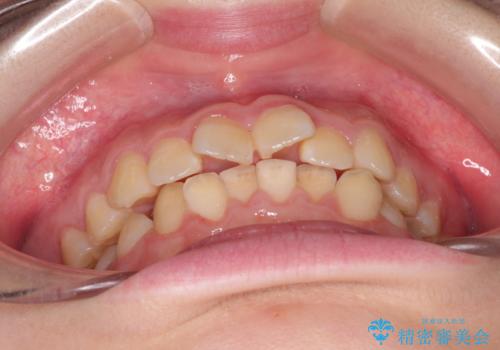

- 上下の前歯のガタガタを治したいとのことで来院されました。

お友達がインビザラインによるマウスピース矯正を行っているとのことで、マウスピースでの治療を希望されました。

上下の歯と歯の間をわずかに削り、並べる計画としました。